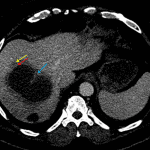

• Large fluid density structure in hepatic segments 7 and 8 measuring 10 x 7 x 7 cm with internal septation and circumferential ill-defined low density compatible with edema

• Peripherally enhancing subcapsular collections along the anterior margin of the left hepatic lobe measuring 3 x 1 cm and 2 x 1 cm

• Hepatic abscess

Acute sigmoid diverticulitis complicated by a small contained perforation and a large abscess in the right hepatic lobe. Additional small subcapsular abscesses along the anterior margin of the left hepatic lobe.

• The classic CT imaging appearance is a double target sign with internal low density surrounded by an internal enhancing rim (capsule) and a low density external rim (edema)

Hepatic abscess showing the double target sign with low density internally surrounded by a thin inner enhancing rim (red arrow) and ill-defined outer low density rim (yellow arrow). Blue arrow indicates an internal septation. Red arrows: additional smaller subcapsular abscesses. Red arrow: focal contained perforation associated with diverticulitis.